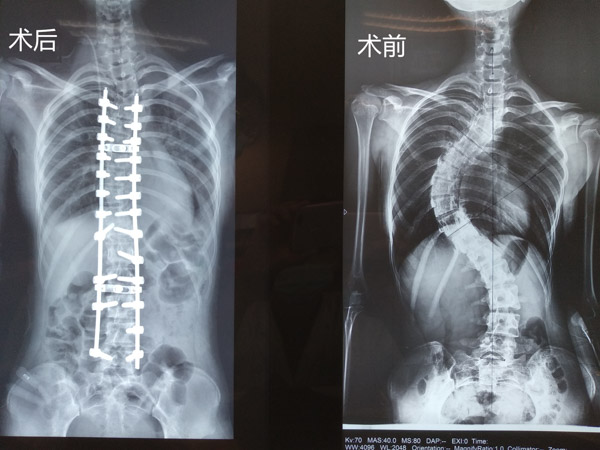

据我院脊柱外科主任胡朝晖介绍,小孔来院检查时脊柱侧凸畸形非常严重,已经对女孩的日常生活造成了严重影响,且畸形极可能进一步加重,压迫心脏、肺、腹部等脏器,引起呼吸困难等心肺腹问题,还可能会出现顽固性背痛、站立和行走困难、跛行、肢体无力、大小便失禁等症状,必须通过手术对其脊柱侧凸畸形进行矫形、固定。

“患者椎骨结构异常,椎体旋转,椎弓根细小,均会导致术中置钉难度大大增加,且患者肺功能已受限,手术矫形后,两肺空间重新分布,两侧胸腔大量积液会加重呼吸困难、甚至危及生命……”面对这一系列的困难,脊柱外科医疗团队为小孔设计了多套应急预案,做好充分准备来应对可能出现的所有情况,确保手术万无一失。

几天后,脊柱外科医疗团队顶着巨大的精神压力为小孔进行脊柱侧弯矫正术,术中置入26枚螺钉,历时近7小时,手术非常成功,麻醉清醒后,小孔的双腿可以自如活动,此刻包括胡朝晖主任在内的所有医护人员都打心眼里为她高兴。

术后恢复期,在脊柱外科护理团队的精心呵护下,小孔的状态一天比一天好,当她第一次下地活动,惊喜地发现自己的背竟然挺起来了!医务人员告诉她,她足足长高了6公分!小孔激动得热泪盈眶:我终于和其他同学一样了,感谢各位叔叔阿姨!